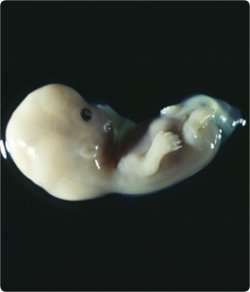

Gelelim Operatör Doktor Orhan'ın durumuna... Mevzu derin... Ama bir kaç kelime de onun için edelim... Sperm canlı bir varlık... Kuyruğunu sallaya sallaya gidiyor, yumurtayı döllüyor.... Yumurta da canlı bir varlık ki, bölünerek büyüyor... Sperm yumurta içinde eriyor, kayboluyor... Canlı yumurta ne zaman canlı bir cenine, insana dönüşüyor?..Ruh ne zaman bedene bağlanıyor?.. İlkahta mı? Yâni döllendiği anda mı?.. Bir hadiste ifâde edildiği gibi 40 gün sonra mı?.. 3 Ay, 90 gün sonra mı?.. Başka bir hadiste öne sürüldüğü gibi 4 ay, 120 gün sonra mı?

- "Andolsun biz insanı (ÂDEM'i) çamurdan (süzülmüş)

bir hülâsadan yarattık. "

(Mü`minûn Sûresi , 12. Âyet )

Bu kısım bizi şimdilik ilgilendirmiyor... Devam edelim âyete:

- "Sonra onu (Hz. Âdem`in nesli olan) insanı

sarp ve metin bir karargâhta (rahimde) bir nutfe (zigot) yaptık.

Sonra o nutfeyi alâka (yapışan şey) hâline getirdik

Derken o alâkayı mudga (bir çiğnem et) yaptık.

O bir çiğnem eti kemik(lere) çevirdik (ve) o kemiklere de et (kaslar) giydirdik.

Sonra onu başka yaratılışla inşâ ettik (can verdik, konuşma verdik)..."

(Mü`minûn Sûresi, 12-14. âyetler)

Bunu açıklayan bir hadis rivâyeti var,

- "Nutfe, rahimde 40 gece kalır. Sonra melek ona şekil verir."

5 haftadan önce kürtaj yapılmıyacağı söyleniyor ki, 35 gündür, 40 ta olabilir. HADİS'e göre NUTFE dönemidir.

Beş haftalık gebelikte, 35-40 günlük bebeğin boyu 1-3 mm civarındadır.

Kilosundan bahsetmek henüz mümkün değildir. Ultrason ile görülebilir, kalp atışları bazen

duyulabilir. Bebeğin beyin, kalp-damar ve sinir ve diğer organ sistemleri gelişmeye başlar.

(linkten alıntı)

Milimetrik varlıkta organlar gelişmeye başladığına göre ruhun bağlandığını düşünebiliriz.